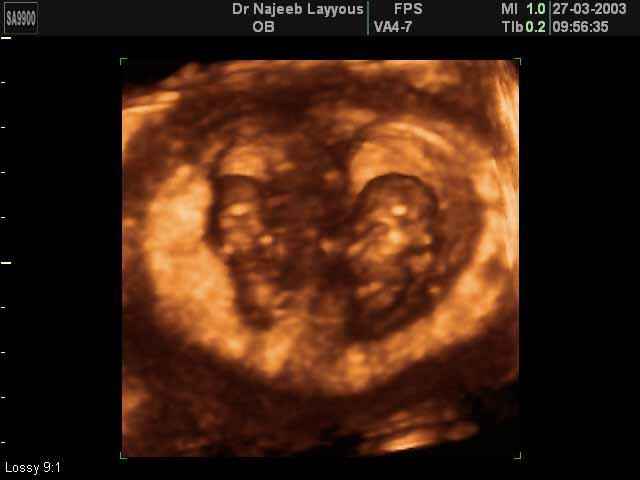

- 3D Photos échographie de grossesse multiple

3D Photos échographie de grossesse multiple : Jumeaux, triplés et quadruples| Dr N Layyous